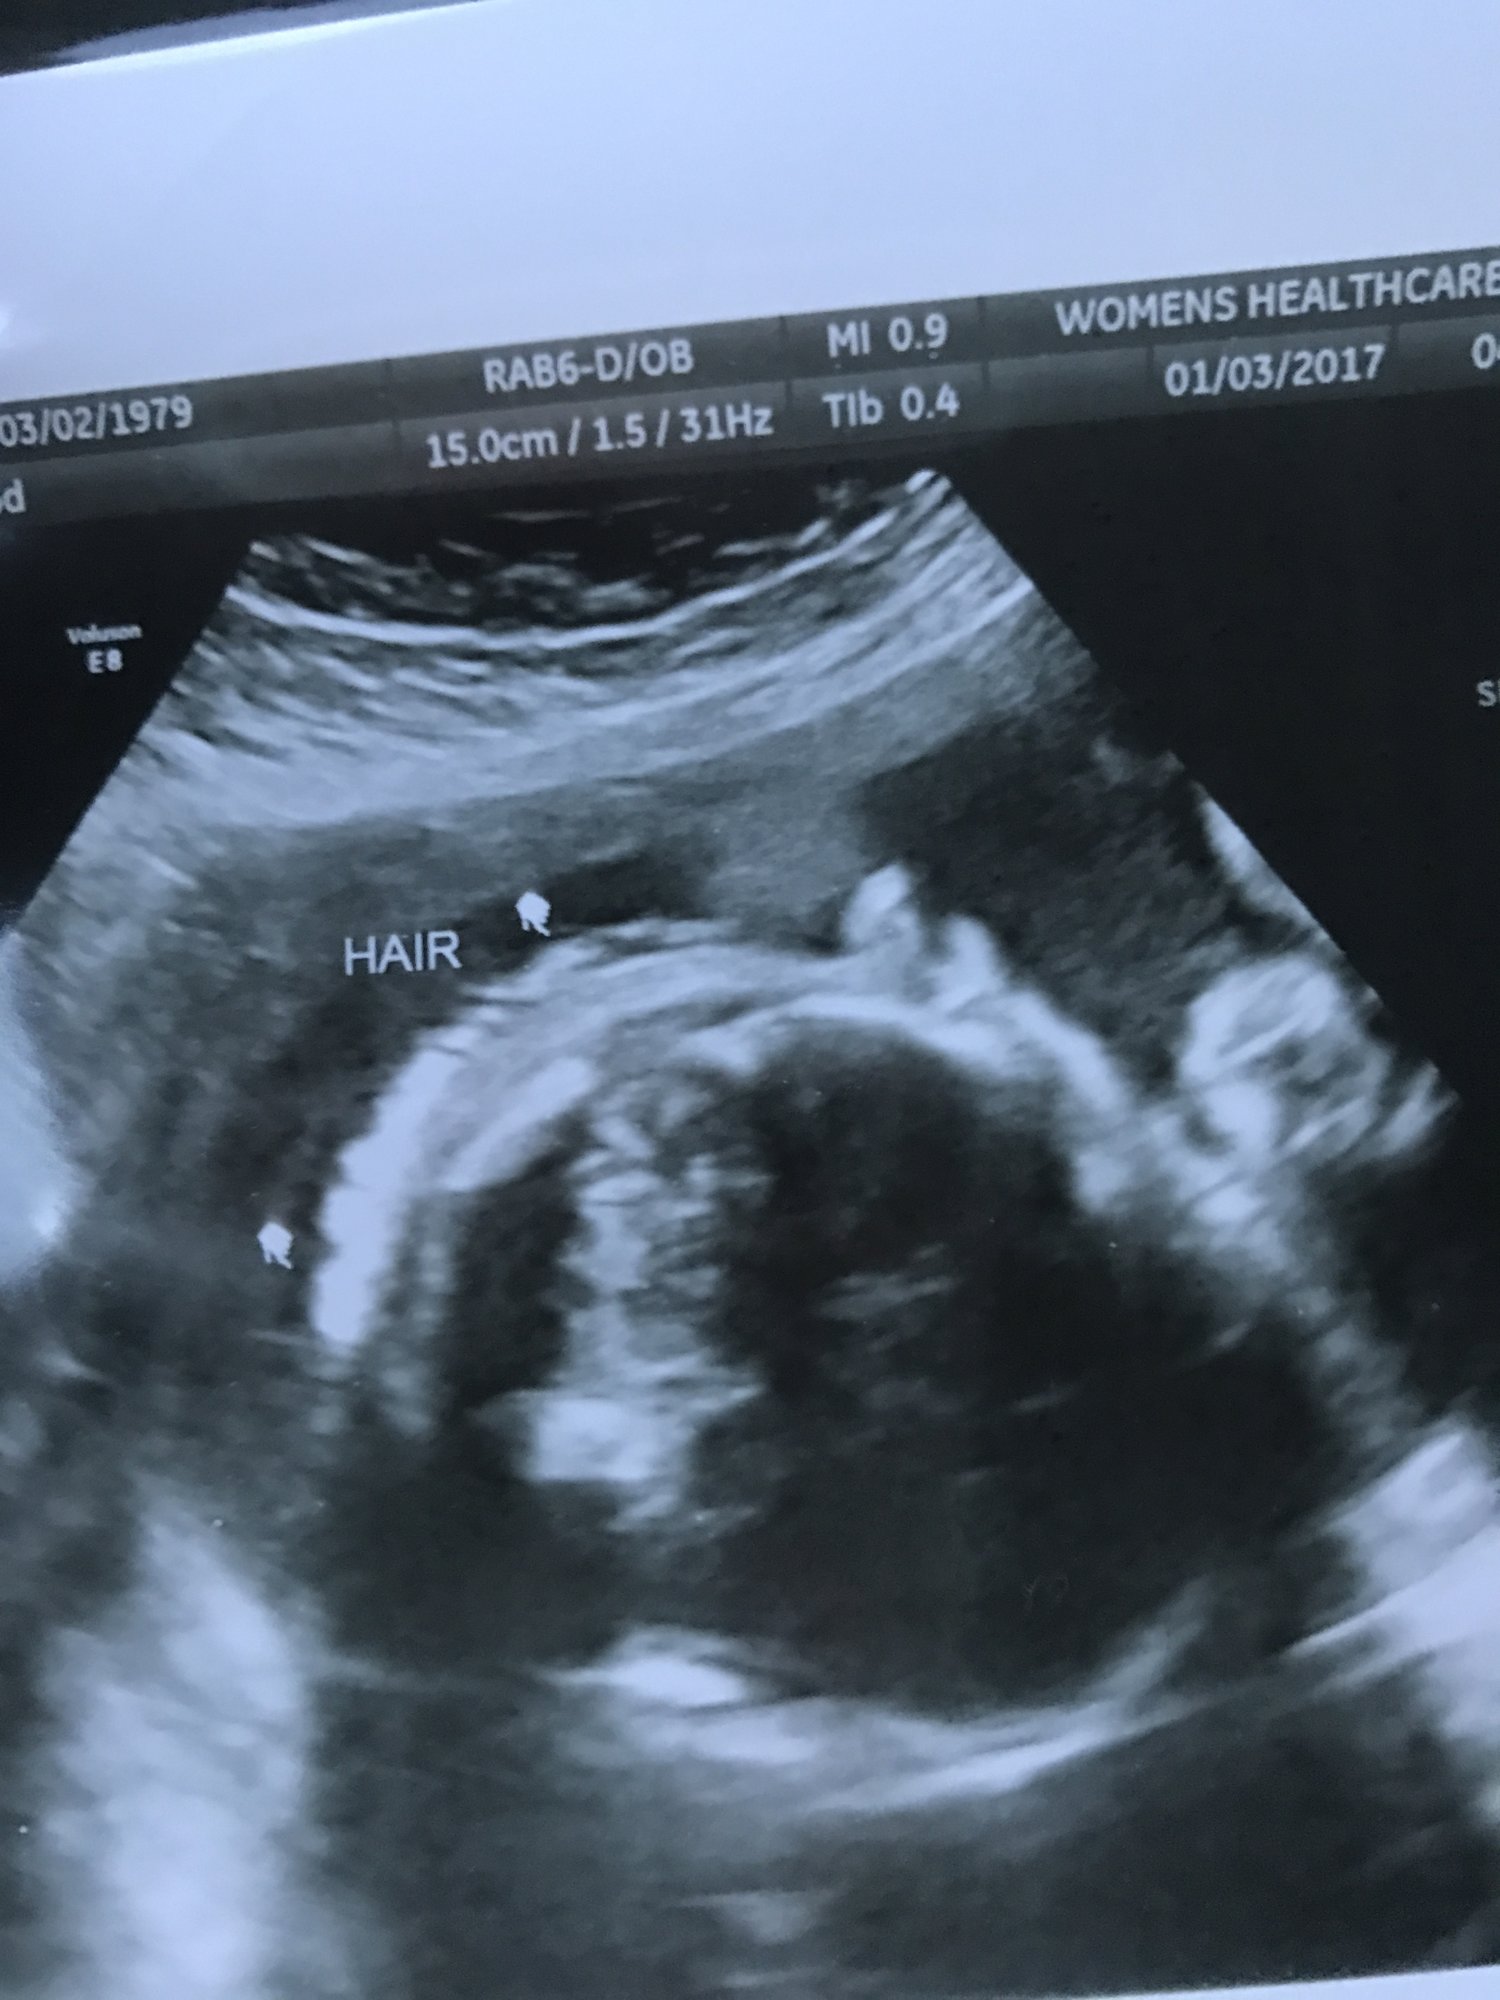

My little lady has a single umbilical artery so we had a growth check today at 28w. She was 2lb10oz and 55th percentile. So far so good. She wouldn't show her face though! We did get this hilarious pic. Explains my raging heartburn....